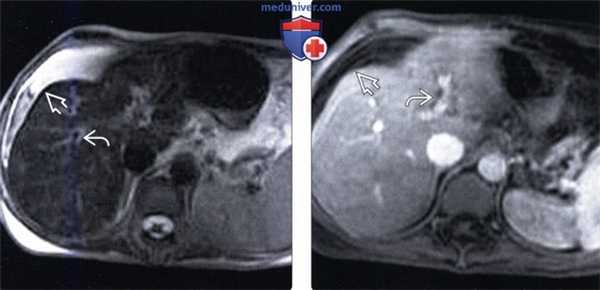

(Слева) На аксиальной Т2 ВИ МР томограмме у женщины 43 лет, страдающей веноокклюзионной болезнью, после курса химиотерапии по схеме FOLLOX по поводу рака червеобразного отростка, определяется асцит и перипортальный отек, которые сами по себе не являются специфическими находками. При исследовании биоптата печени были подтверждены застойные изменения в синусоидах и фиброз венул.

(Справа) На аксиальной Т1 ВИ МР томограмме с контрастным усилением у этой же пациентки определяется асцит и перипортальный отек.2. МРТ признаки веноокклюзионной болезни печени: